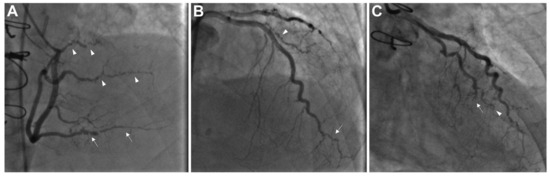

3. Invasive Coronary Angiography